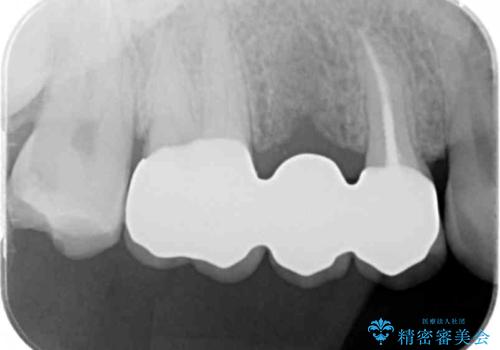

- 他院でブリッジの仮歯を入れたが、外れやすいため転院を希望された患者様です。

支台歯の形が角度が大きくついた形に形成してあり、外れやすい形になっていたため修正してから歯型をとりました。

- 36.3万円(ジルコニアクラウン10万円x3本)費用は治療当時の料金となります

根の治療のやり直しは特に行っていません。